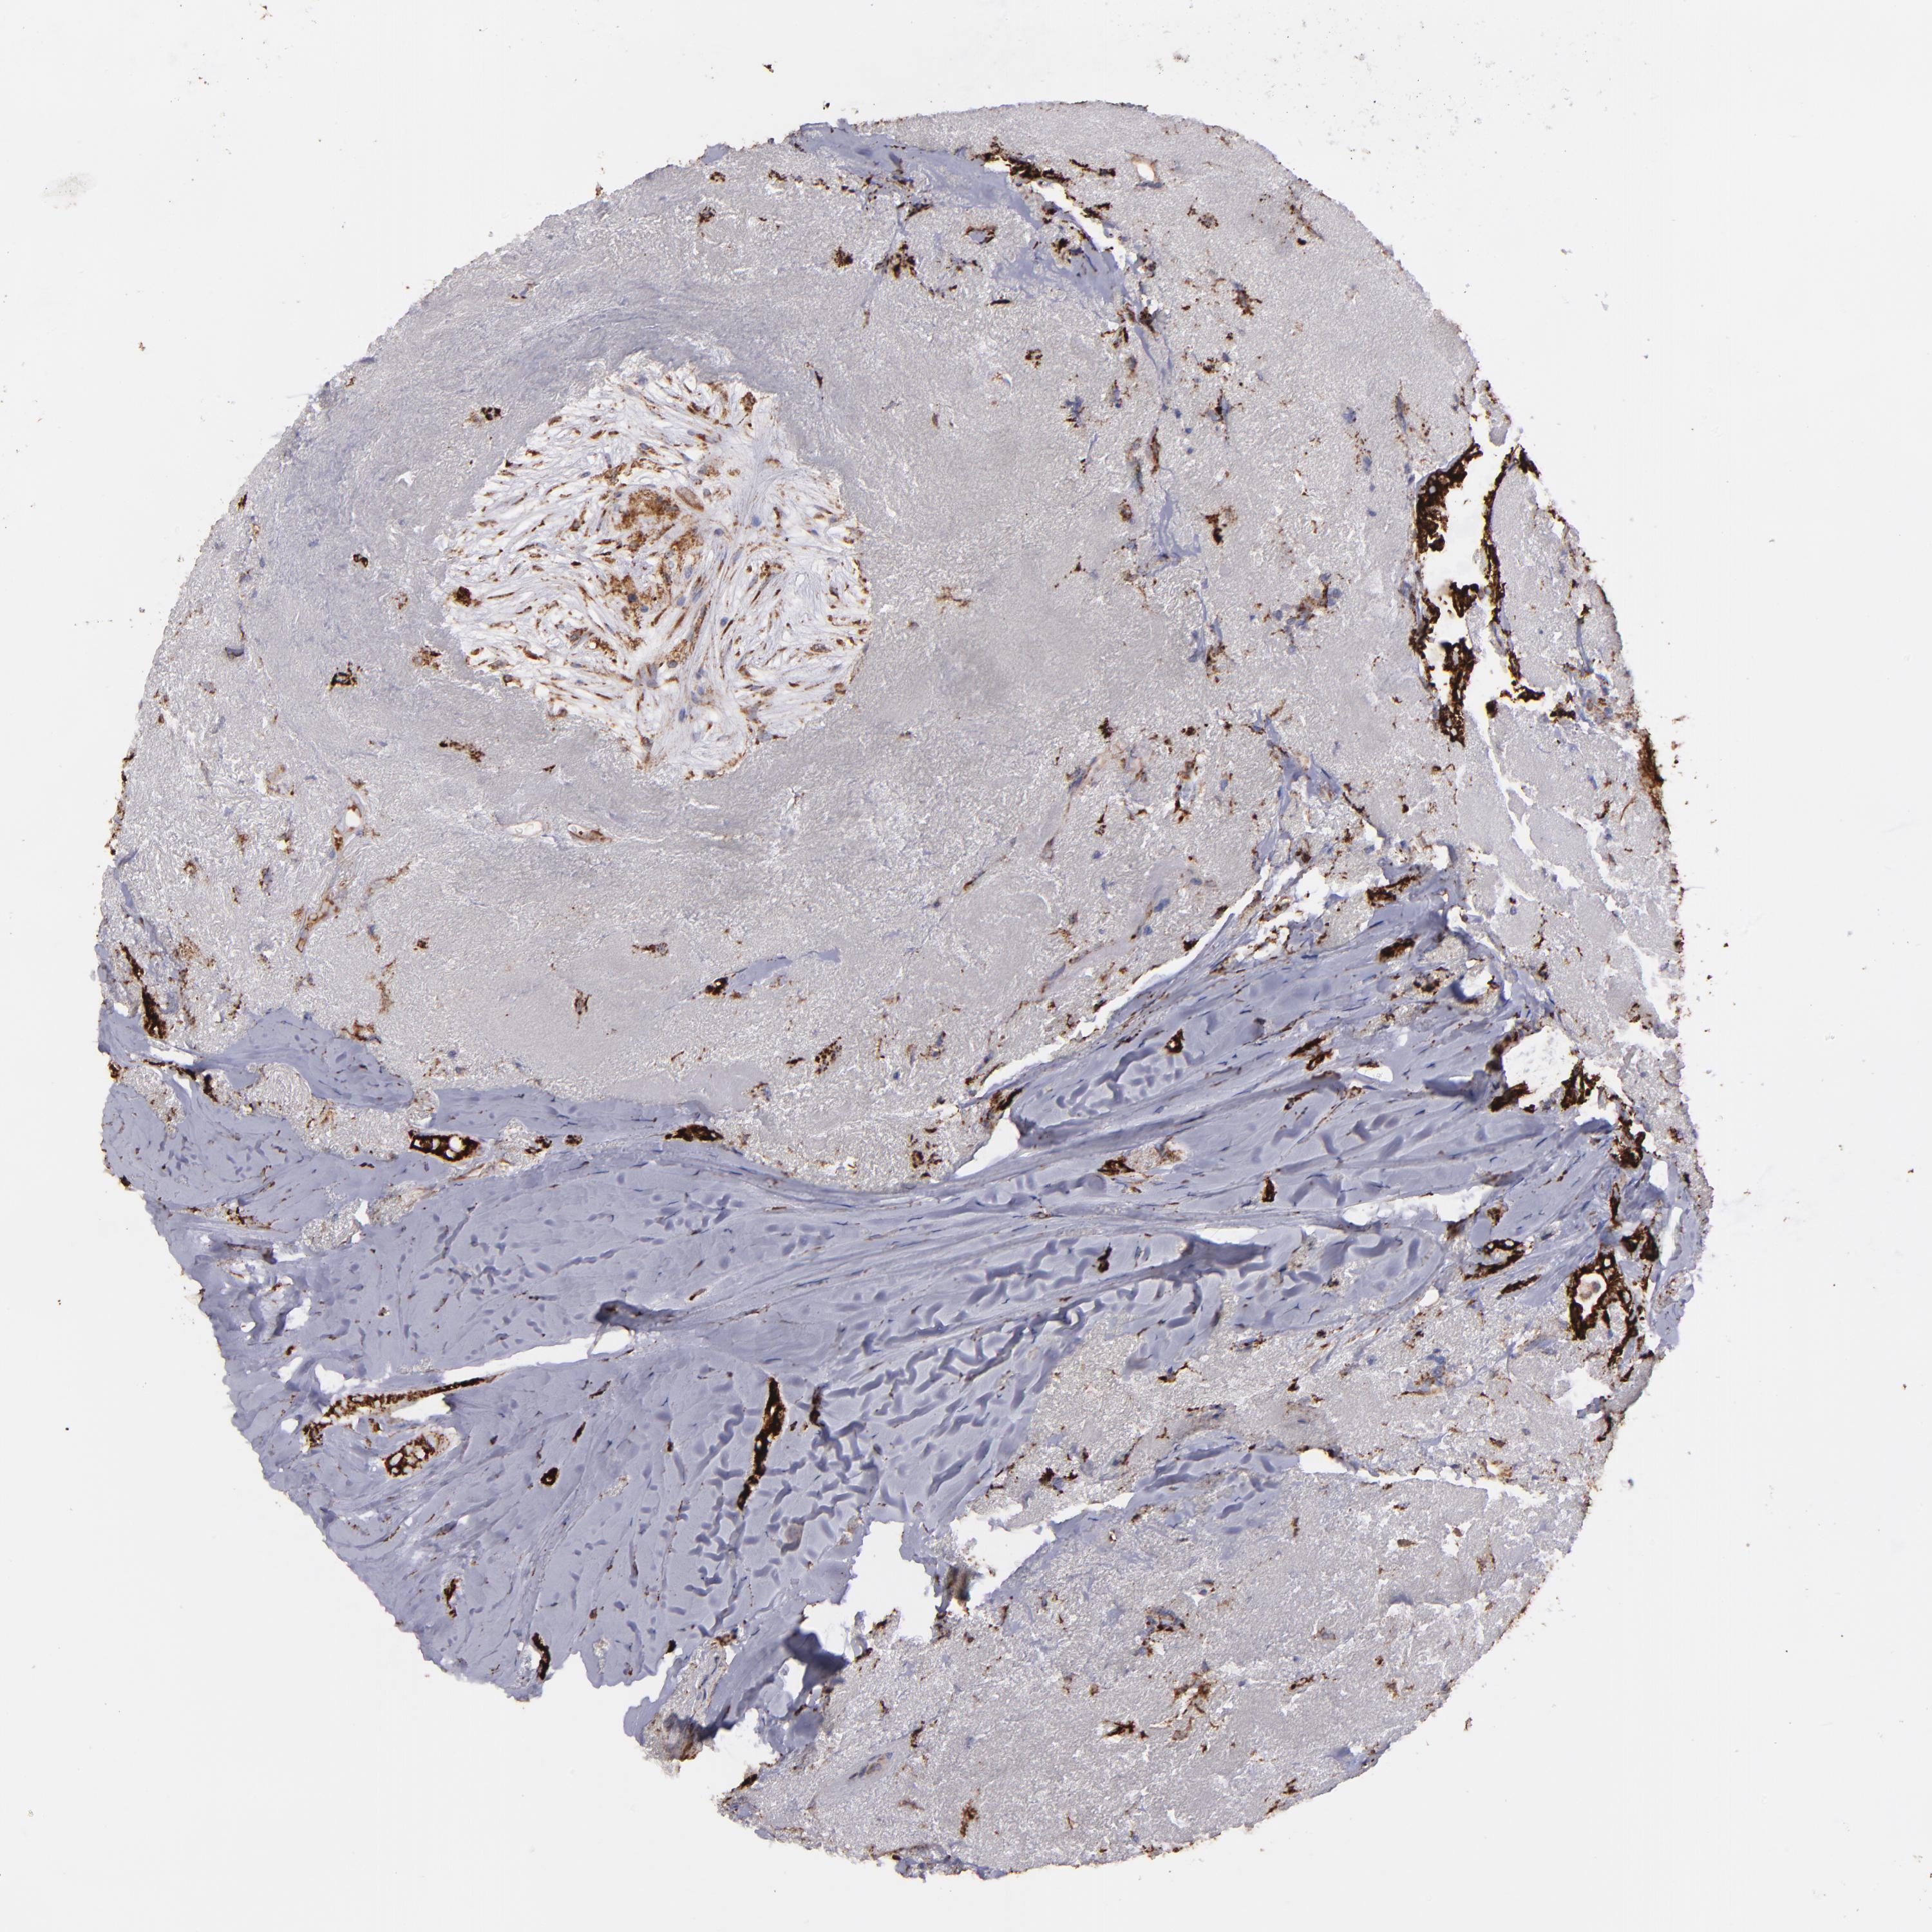

BRCA TCGA BRCA VALIDATION PROTEIN EXPRESSION